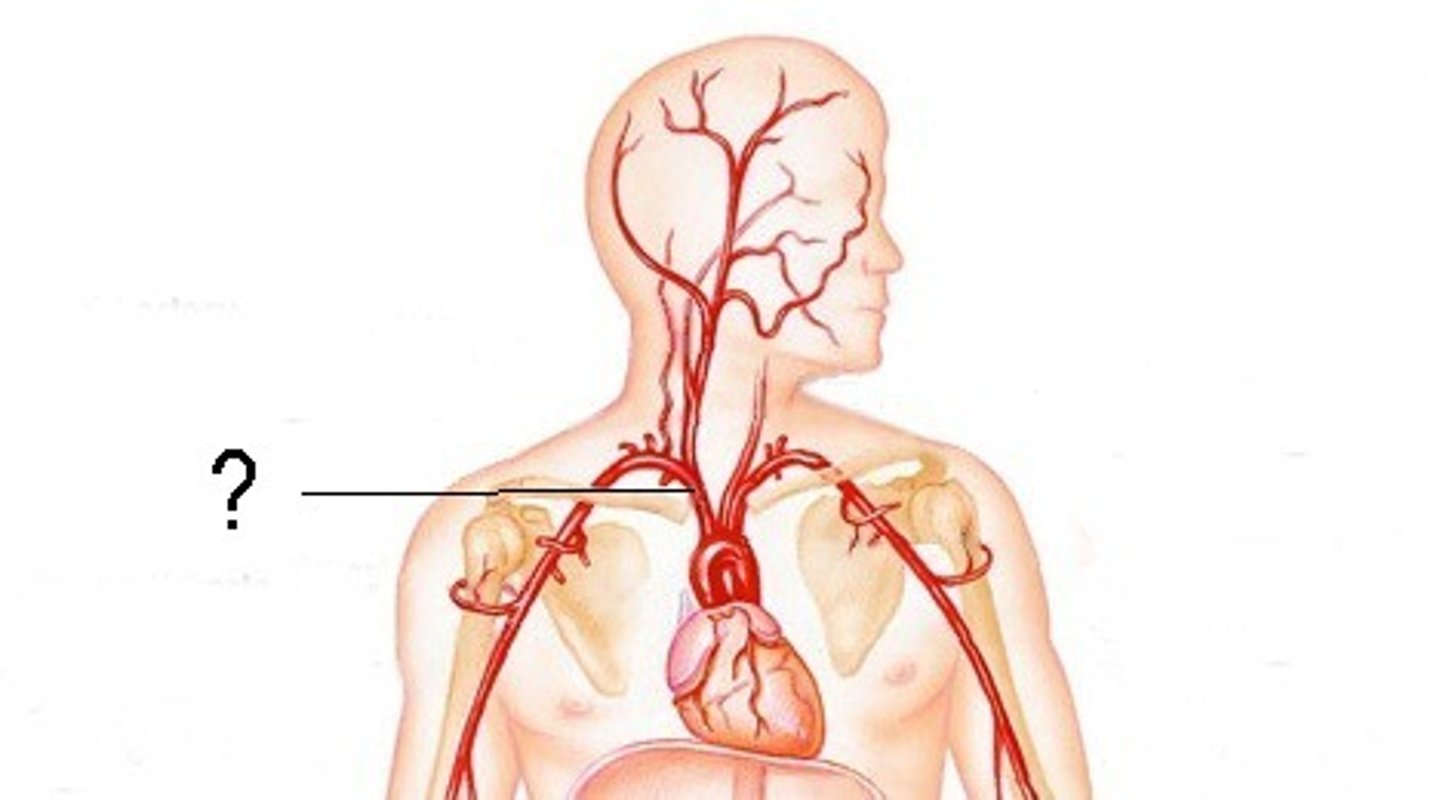

brachiocephalic artery

feeds right common carotid artery and right subclavian artery

aortic arch

feeds brachiocephalic artery, right and left common carotid arteries, right and left subclavian arteries

right subclavian artery

left subclavian artery

Right common carotid artery

left common carotid artery